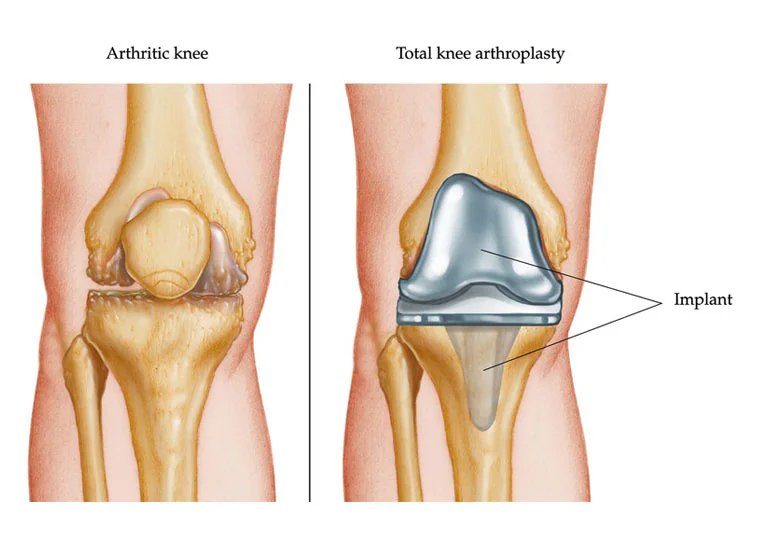

Knee and hip replacement surgeries involve removing damaged parts of the joint and replacing them with artificial components. These procedures aim to alleviate pain, restore function, and improve the quality of life for individuals suffering from severe joint issues.

- Joint Deformity or Damage

- Knee Replacement: Severe joint damage or deformity, such as bowed legs or significant cartilage loss, can be indications that knee replacement is needed.

- Severity of Joint Damage: X-rays and MRI scans can reveal the extent of damage to your knee or hip joint.